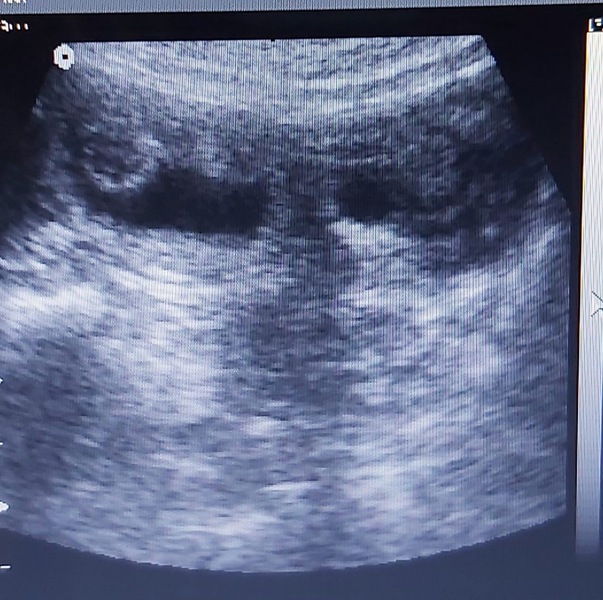

Mit Freude geben wir die Trächtigkeit unserer Bea bekannt, die der Ultraschall heute bestätigte.

So alles weiterhin gut verläuft,  erwarten wir Mitte Februar vielversprechende  Welpen in zw u. tricolor von